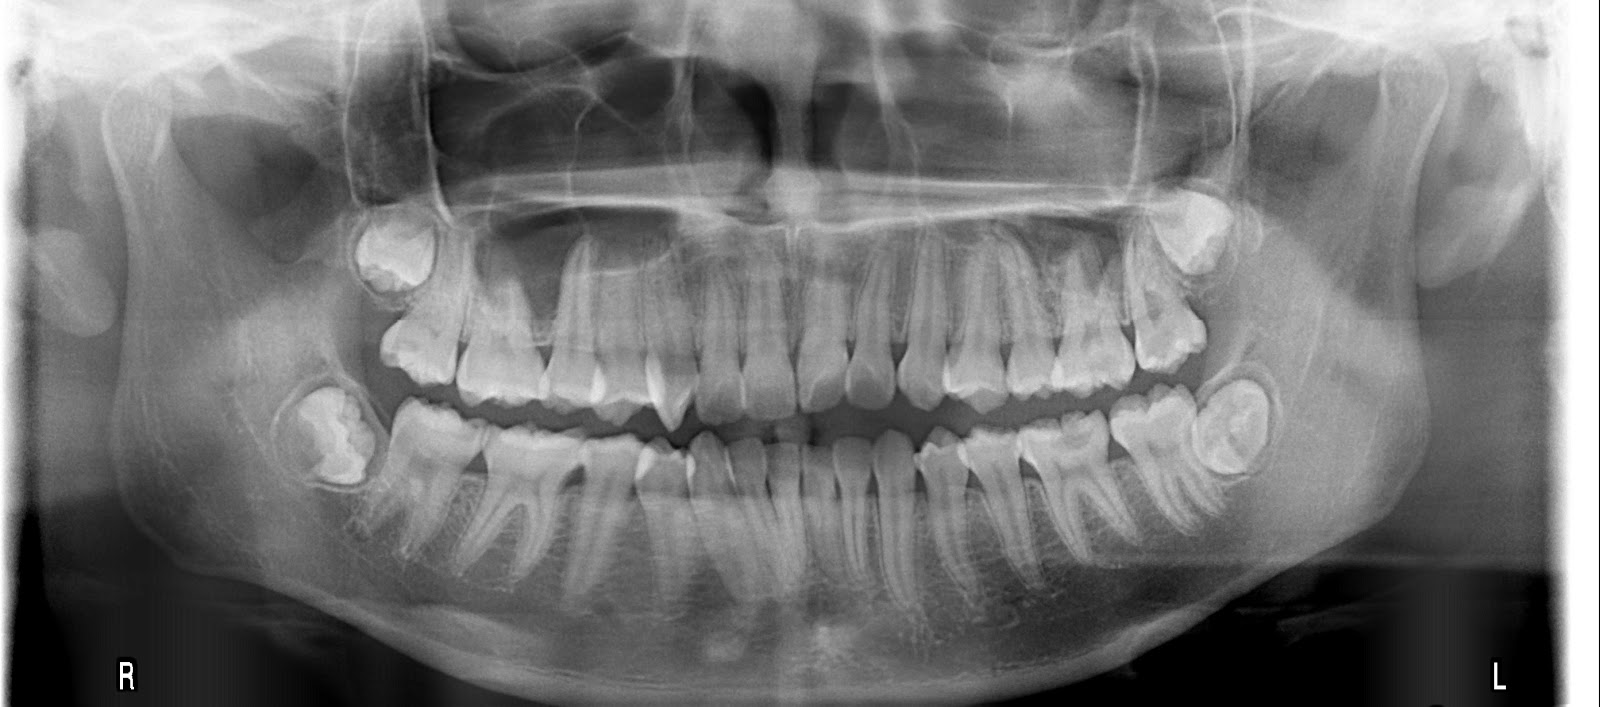

評估的項目還包括 : 用全口X光機或電腦斷層設備,檢查骨質密度及萎縮程度、齒槽骨的高度、寬度可不可以馬上作植牙手術?不夠的話也可以先行補骨粉等待數月後再植牙,或植牙與補骨同時進行。

適合植牙的年紀?

★ 全口低輻射數位X光機